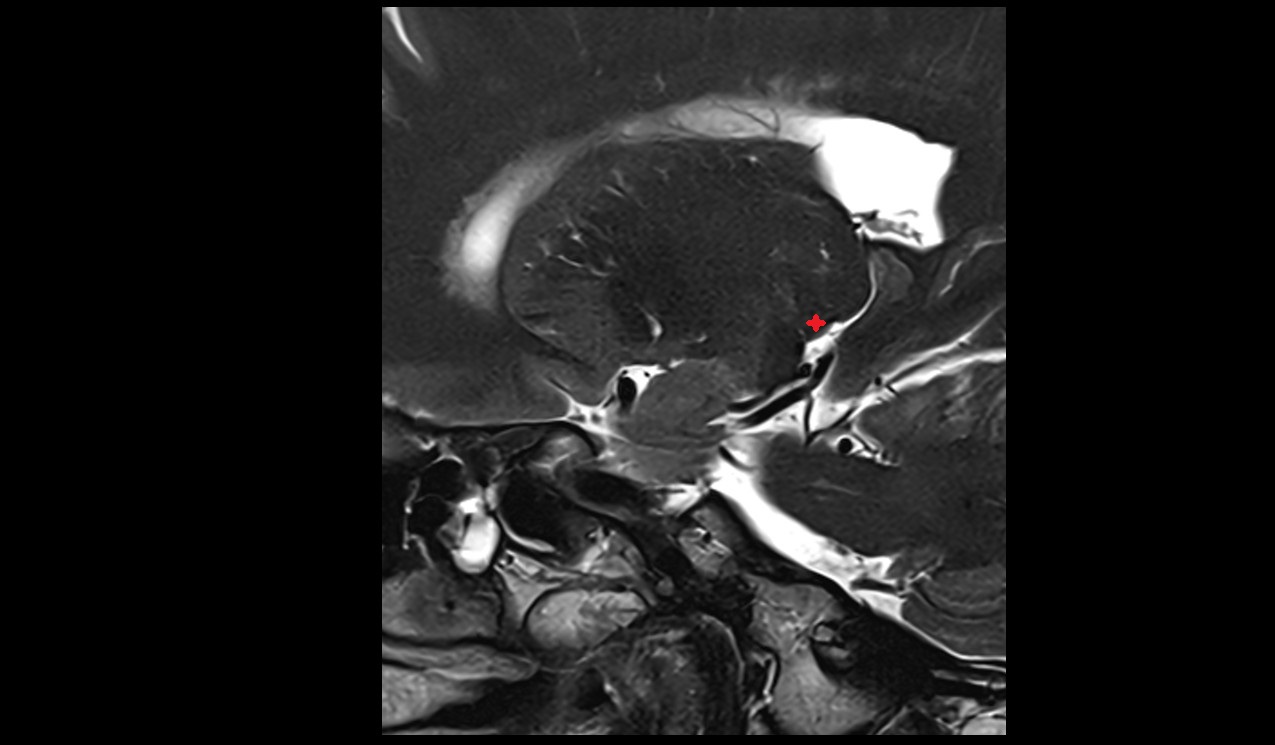

- Temporomandibular joint

- Articular disc of temporomandibular joint

- Mandibular condyle

- Articular eminence

- Intermediate zone of articular disc